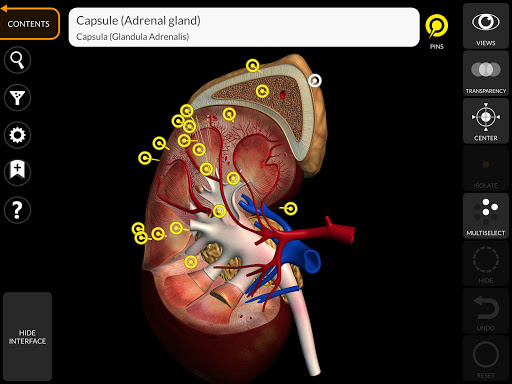

"Anatomy 3D Atlas" vous permet d'étudier l'anatomie humaine de manière simple et interactive.

Grâce à une interface simple et intuitive, il est possible d'observer chaque structure anatomique sous n'importe quel angle.

Les modèles anatomiques 3D sont particulièrement détaillés et avec des textures jusqu'à une résolution de 4k.

La subdivision par régions et les vues prédéfinies facilitent l'observation et l'étude de parties individuelles ou de groupes de systèmes et les relations entre différents organes.

MODÈLES ANATOMIQUES 3D

• Système endocrinien